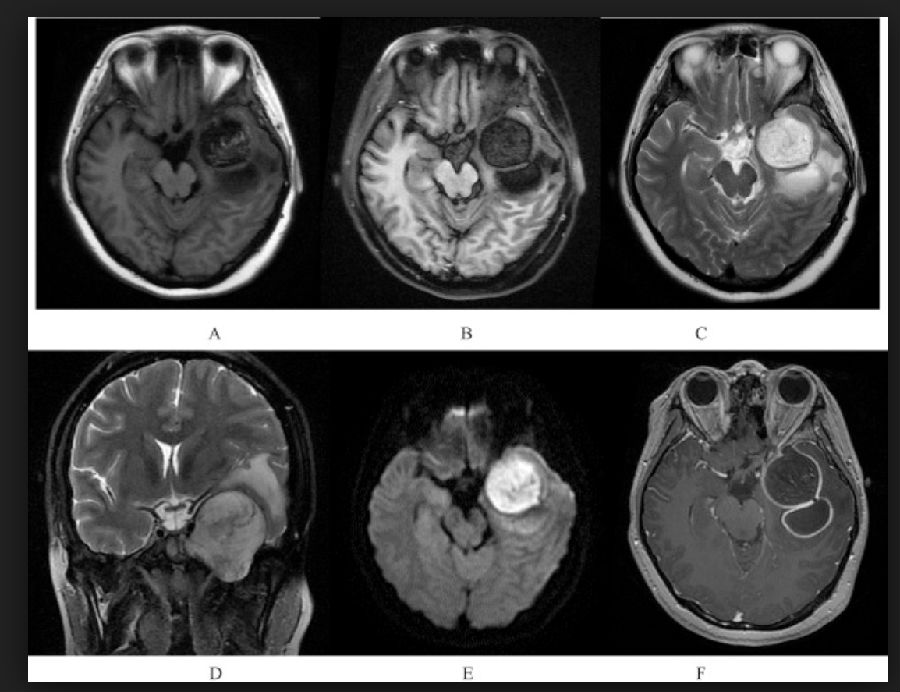

颅内囊性病变(Intracranial cystic lesions,ICL)相信大家并不陌生,首先先放几张图,大家猜一下是什么疾病,答案文末揭晓。

图1 脑内皮样囊肿

图2 脑脓肿

图3 扩大的血管周围间隙

图4 星形胶质细胞瘤

图5 表皮样囊肿